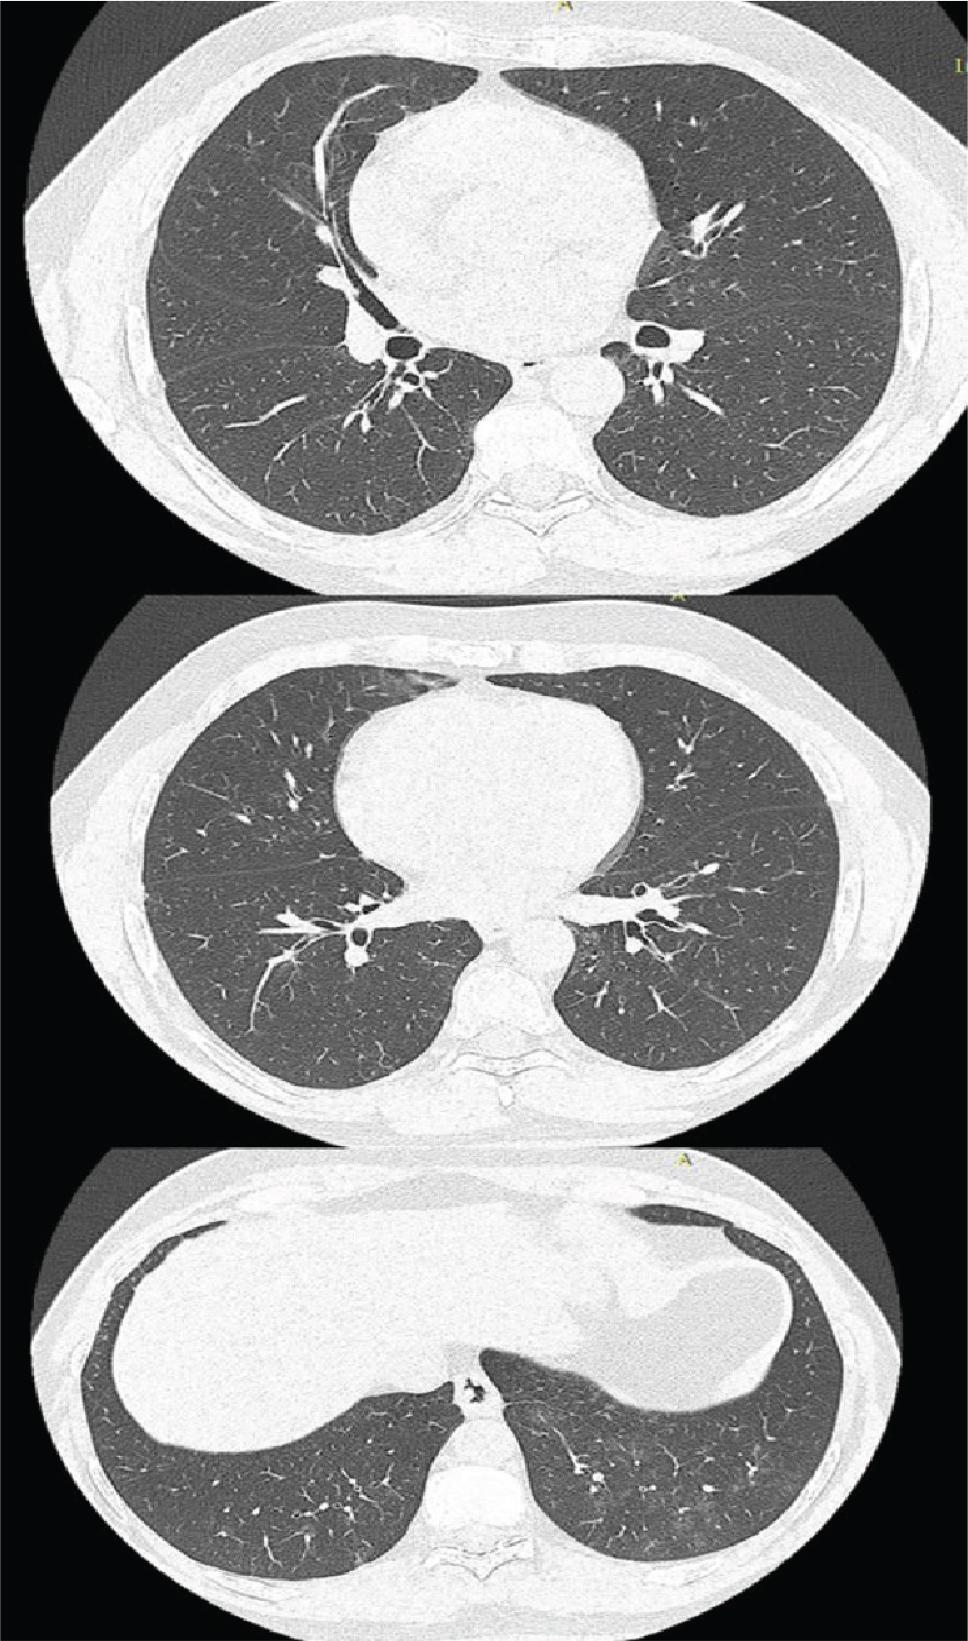

Chest computed tomography re-evaluation after one month of antituberculosis treatment (ATT) showed quasi-complete regression of the pulmonary condensation areas and groundglass areas in the lower lobes (Figure 2).

Chest CT with quasi-complete regression of pulmonary condensation areas.